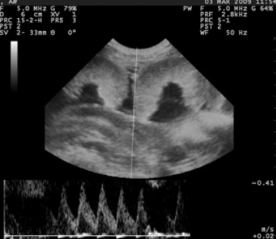

羊用B超机对山羊胎儿心率(FHR)

心跳频率可以通过高科技超声(图5)的胎心率下降)。一种据报告,FHR的下降趋势相似山羊怀孕。FHR与据报道埃及原生山羊的胎儿年龄(r=0.55)和Saanen山羊(r=0.77)(图6)

图5测量的胎心率从脐带的动脉在妊娠130天和脐带横切面

心脏的长轴和短轴在绵羊中,胎儿心脏在第44-63天清晰可见妊娠,心脏腔和瓣膜明显不同从妊娠第97天到第103天有危险。2007年报告了一个高相关性羊胎心直径与GA之间的关系在怀孕40到100天之间。长和胎儿心脏的短轴应从舒张期四腔切面的横截面胎儿身体运动缺乏的状态耳鼻喉科。据我们所知,只有一项关于胎儿心脏的研究直径和GA在山羊。根据从绵羊胎儿研究中获得的结果es,它有一个与长轴和短轴以及GA高度相关(分别为r=0.91和r=0.88)。